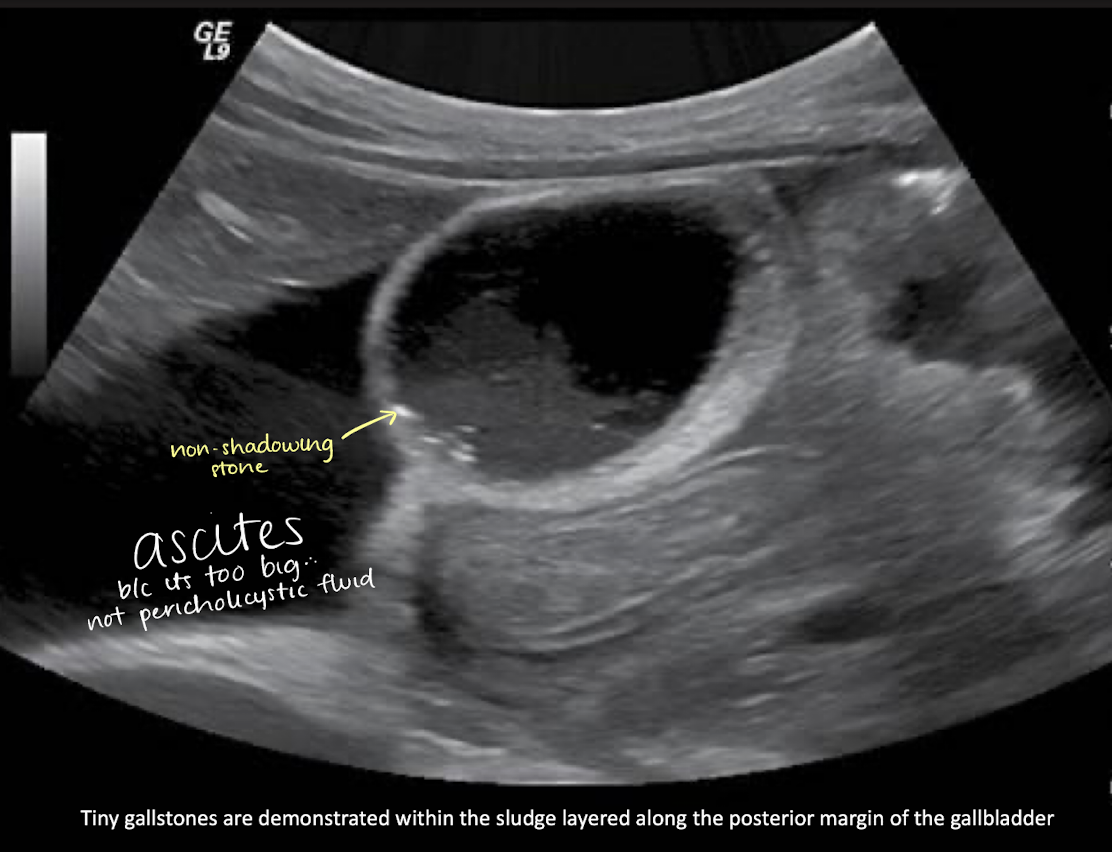

cholelithiasis

tiny stones along sludge layer + ascites